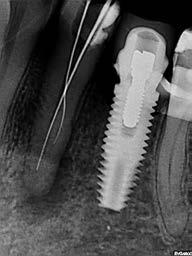

This element was not stimulated with the cold test and the radiographic image revealed an incomplete endodontic treatment (Figs. 1-2). The element seemed to present a suitable root length for a conservative restoration, but the apical position of the carious lesion and the proximity of the interdental bone ridge didn’t allow a correct rehabilitation with prosthetic crown, respecting the biological width.2

Figure 2: Initial radiograph showing endodontic dressing that had been present for some months, but the treatment was never completed. Note the depth of the caries lesion and the proximity of the interdental bone ridge, which may represent an obstacle for prosthetic rehabilitation.

The canal was sealed with a Thermafil™ cone (Dentsply Sirona) with an apical diameter of 0.30 mm (Figs. 3-4).

glass fibre Figure 3: Root canal therapy completed under proper isolation. Figure 4: Radiography of completed root canal therapy and reconstruction made completely in glass hybrid cement. Figure 5: Clinical crown lengthening with a minimally invasive technique without mesial and distal discharges. Note the proximity of the reconstruction in glass hybrid material to the mesial bone ridge. Figure 6: Suture at the end of surgical therapy. It was left in place for 7 days Figure 7: Suture removal at 7 days. Post-surgical edema is still present.

Figure 12: Final radiography after positioning of the endodontic post, composite reconstruction and insertion of the provisional crown in PMMA. Note the distance between the edge of the cement used to fix the crown, more radiopaque than PMMA, and the new bone ridge created with periodontal surgery.